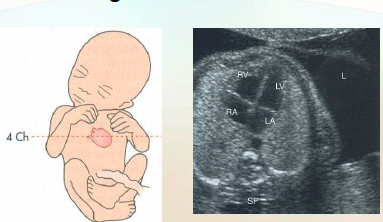

Transverse of 4 chamber heart

Fetal heart lies more horizontal than the neonatal heart because the lungs are not inflated in utero

This allows for image planes not possible after birth

On transverse 4 chamber heart note the heart

Size: 1/3rd the size of the thorax

Axis: Between 40-45 degrees from the midline

*Should NOT be greater than 45 degrees

Position in thorax: Ventricles pointing toward the left

what is the #1 image to determine if the apex of the heart is correct?

the 4-cahmber heart

how far offof the line you draw from the spine directly anterior should the heart apex be?

45“